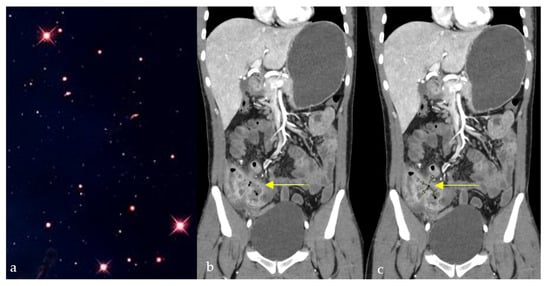

Abdomen and Pelvis

- Giambelluca, D.; Interlicchia, F.; Capodieci, G. The “star sign” in Crohn’s disease. Abdom. Radiol. 2021, 46, 2987–2988. [Google Scholar] [CrossRef]